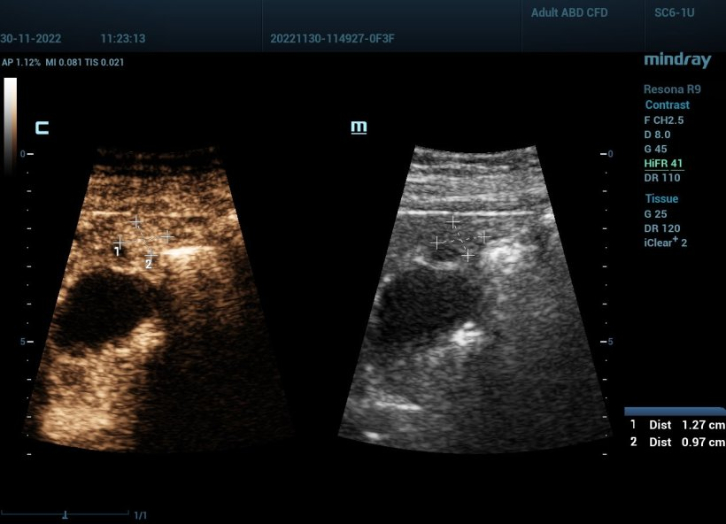

Ultrasonografi kontras (CEUS) adalah bidang yang sangat dinamis dan dalam beberapa tahun terakhir inovasi teknologi telah semakin meningkatkan kualitas gambar. Salah satu inovasi ini adalah ultrasonografi kontras tingkat frame tinggi (HiFR CEUS) yang dapat menghasilkan hingga sepuluh kali lebih banyak gambar dibandingkan ultrasonografi konvensional ŌĆō dalam waktu yang sama. Peneliti di tujuh pusat di Jerman, Swiss, dan Tiongkok sedang mengevaluasi efektivitas HiFR CEUS dalam mendiagnosis lesi hati kecil. Profesor Dr Yi Dong dari Departemen Ultrasonografi, Rumah Sakit Xinhua, Shanghai Jiaotong University School of Medicine, dan Profesor Dr Christoph F Dietrich, Departemen Penyakit Dalam Umum, Hirslanden Bern, Swiss, menjelaskan latar belakang dan tujuan dari studi ini.

Yi Dong: 'Tujuan utamanya adalah diagnosis yang lebih presisi dari lesi hati fokal dengan diameter kurang dari 3 cm pada pasien dengan dan tanpa sirosis hati. Studi sebelumnya telah menunjukkan bahwa HiFR CEUS memvisualisasikan pola dan morfologi pembuluh darah pada lesi tersebut dengan sangat baik. Kami mengharapkan HiFR CEUS dapat menawarkan resolusi temporal dan spasial yang lebih baik, dengan kata lain gambar berkualitas lebih tinggi dari lesi hati yang sangat kecil. Ini akan meningkatkan kepercayaan dalam karakterisasi dan diagnosis lesi ini. Penelitian sebelumnya tentang karsinoma hepatoseluler (HCC) telah menemukan bahwa ada perbedaan yang cukup signifikan apakah lesi kecil tersebut terletak pada latar belakang hati sirotik atau pada hati yang sehat.'

Yi Dong: 'Dalam sistem ultrasonografi konvensional, tingkat frame dalam pencitraan kontras non-jantung adalah sekitar sepuluh frame per detik. Sistem HiFR CEUS yang kami gunakan, Mindray Resona 9, jauh lebih cepat: dapat menghasilkan hingga 100 gambar per detik. Tingkat frame yang tinggi seperti ini menawarkan visualisasi yang lebih baik dari morfologi vaskular dan menunjukkan detail perfusi mikrovaskular serta pelacakan gerakan yang lebih baik. Singkatnya: ini meningkatkan efisiensi diagnostik CEUS. Dalam studi kami, kami akan fokus pada arsitektur vaskular selama fase arterial CEUS, fase wash-in awal, waktu peningkatan kontras, eliminasi, dan pola yang relevan.'

Christoph Dietrich: 'Sekitar 70% dari total aliran darah hati melalui vena porta yang membawa nutrisi dan produk metabolik dari saluran pencernaan serta racun untuk detoksifikasi ke hati. Darah arterial juga menyediakan 30% oksigen. Ultrasonografi hati kontras dengan demikian menggunakan fase arterial serta fase vena porta untuk menghasilkan gambar. Dalam hati sirotik, vena porta rusak dan darah tidak lagi dapat didetoksifikasi. Jadi, terkait pencitraan, fase vena porta menawarkan informasi yang lebih sedikit. Oleh karena itu, studi kami akan fokus pada fase arterial. Karena tingkat frame yang tinggi, volume data relevan yang tinggi diperoleh meskipun fase vena porta diabaikan. Ini seperti jaring ikan: semakin rapat tenunan jaringnya, semakin banyak ikan yang bisa Anda tangkap. Terkait pencitraan: semakin tinggi kepadatan garis, semakin tinggi resolusinya. Lebih banyak tumor tertangkap dan dapat ditangani sesuai dengan pedoman medis saat ini.'

Yi Dong: 'Kami menggunakan paket perangkat lunak khusus yang disebut VueBox untuk melakukan analisis kuantitatif dari data. Ini memungkinkan kami untuk menangkap kurva intensitas waktu dan memberikan parameter kuantitatif untuk diagnostik masa depan. Kami berharap analisis kuantitatif ini akan memungkinkan kami untuk mendeteksi lesi kecil lebih awal.'